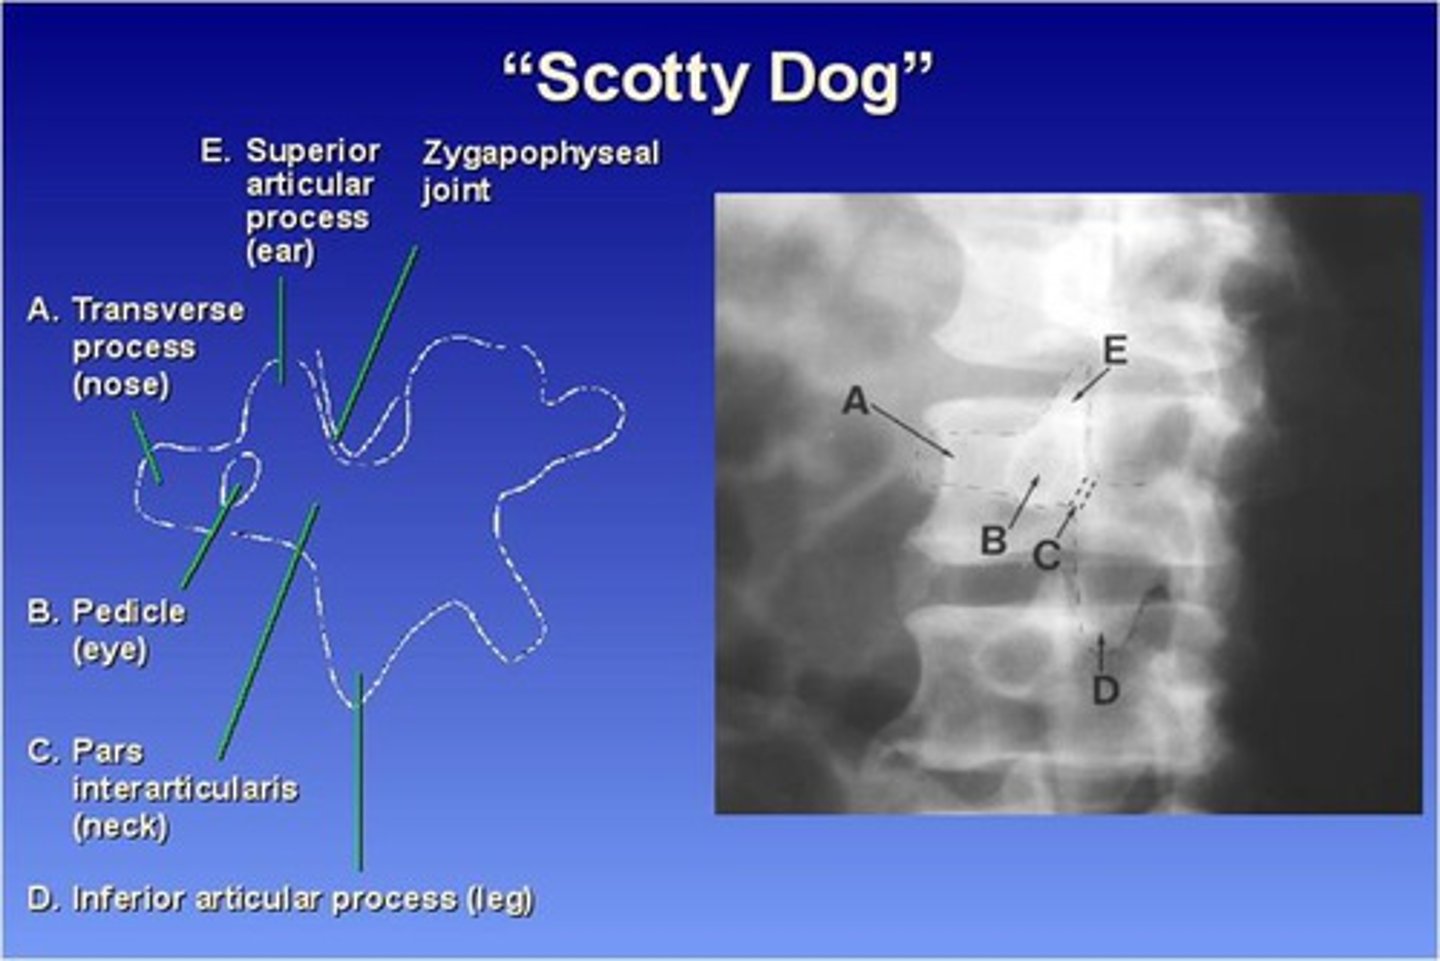

The Lumbar zygapophyseal joints are ONLY demonstrated on what view?

45 degree obliques (will see "scotty dog")

What part of the lumbar spine makes up the "nose" of the "scotty dog"?

transverse process

What part of the lumbar spine makes up the "eye" of the "scotty dog"?

pedicle

What part of the lumbar spine makes up the "neck" of the "scotty dog"?

pars interarticularis

What is the pars interarticularis?

portion of each lamina between the superior and inferior articular processes

What part of the lumbar spine makes up the "leg" of the "scotty dog"?

inferior articular process

What part of the lumbar spine makes up the "ear" of the "scotty dog"?

superior articular process